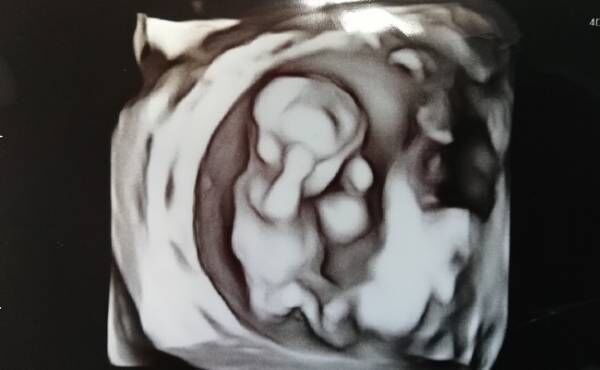

検査当日は、まずエコーをおこないました。

染色体異常の場合、心臓に問題がある場合が多いため、20分ほどかけて念入りにエコーで確認。結果、心臓には異常がなさそうとのことで、NIPTのための採血をしました。